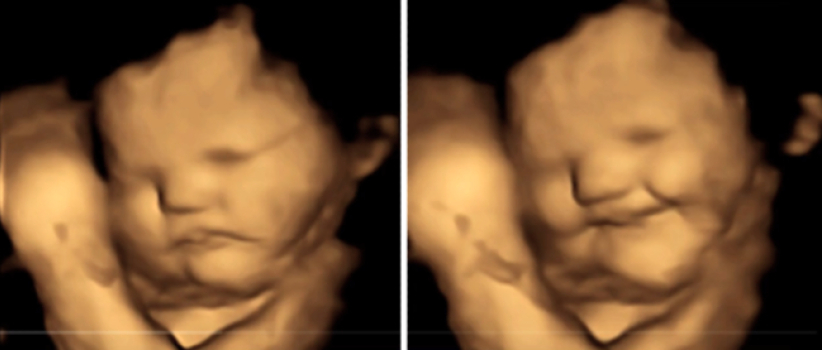

從兩張照片看到,左邊一張是嬰兒休息時候的樣子,右邊是母親吃完胡蘿白後嬰兒皺著眉頭。

節目主持人Jones和嘉賓Dylan Dreyer 討論這怪趣現象時,打趣地笑說可能嬰兒覺得胡蘿白苦味,所以皺起眉頭,這也顯示嬰兒已經能夠控制面部肌肉,作出不同的表情;節目播出後多達70萬人次點擊觀看。